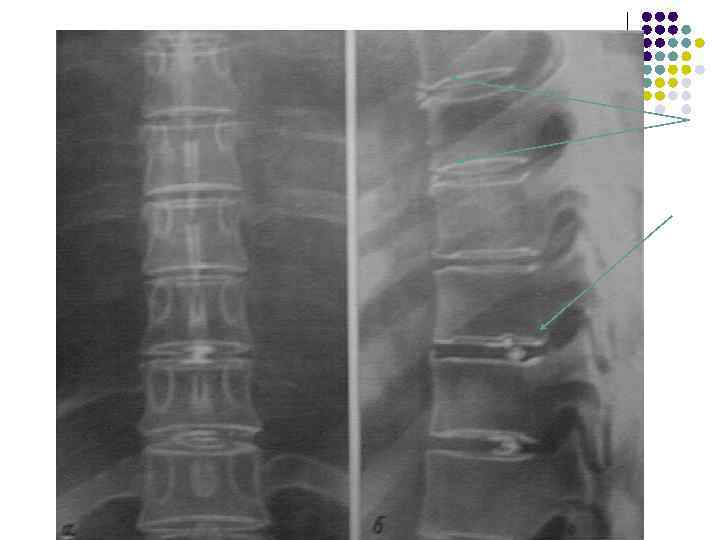

Остеохондроз 1. 2. 3. 4. Кроме почти всех или всех признаков хондроза должны быть обязательно: Краевые специфические костные разрастания – вдоль выпяченного межпозвонкового диска (увеличение площади опоры) Уменьшение высоты межпозвонкового диска Субхондральный остеосклероз (выявить не легко) Сохранение четких непрерывных контуров всех поверхностей тел позвонков.

Degenerative disk disease. The presence of a linear radiolucency in the disk space (vacuum phenomenon) is a typical finding of degenerative disk disease. It is often associated to other findings of degenerative disk disease such as disk space narrowing and endplate sclerosis.

Рентгеновская семиотика. Изменение костной структуры l Деформация замыкательных площадок – грыжи Шморля